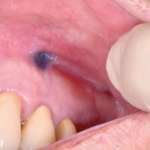

Diagnostica differenziale delle lesioni pigmentate del cavo orale Premium

Le varie localizzazioni e manifestazioni delle pigmentazioni della mucosa orale rendono difficile distinguere quelle attribuibili a malattie sistemiche, a malattie infiammatorie, a neoplasie, a...